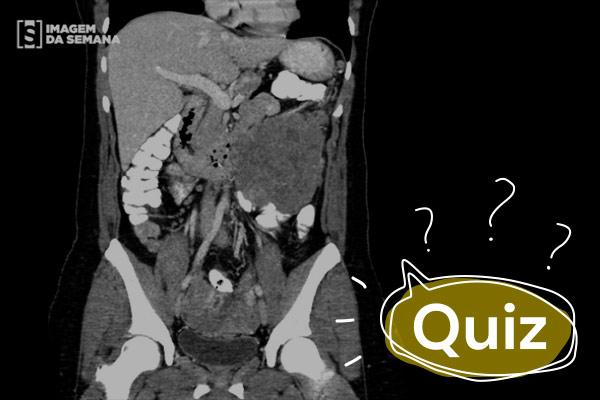

Paciente do sexo feminino com queixa de empachamento pós-prandial, cólicas abdominais e abaulamento do abdome há 6 meses. Qual é a conduta?